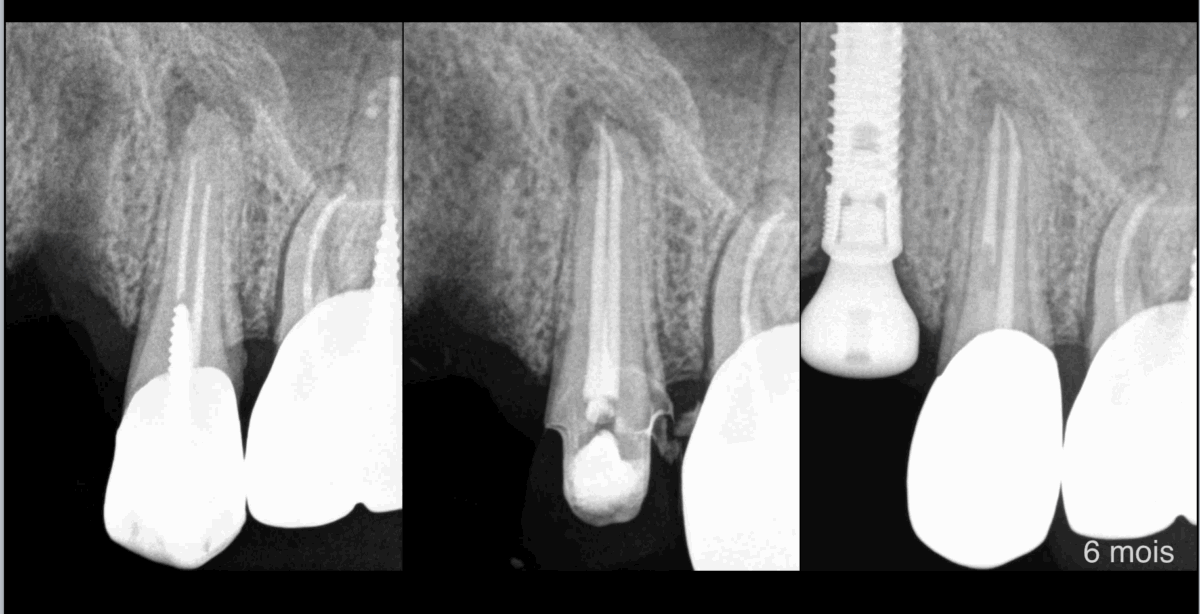

📊 𝐋𝐞 𝐫𝐢𝐬𝐪𝐮𝐞 𝐝𝐞 𝐥𝐞́𝐬𝐢𝐨𝐧 𝐚𝐩𝐢𝐜𝐚𝐥𝐞 𝐝’𝐮𝐧𝐞 𝐝𝐞𝐧𝐭 𝐚𝐝𝐣𝐚𝐜𝐞𝐧𝐭𝐞 𝐚̀ 𝐮𝐧 𝐢𝐦𝐩𝐥𝐚𝐧𝐭 𝐞𝐬𝐭 𝟐 𝐟𝐨𝐢𝐬 𝐩𝐥𝐮𝐬 𝐢𝐦𝐩𝐨𝐫𝐭𝐚𝐧𝐭 𝐪𝐮’𝐮𝐧𝐞 𝐝𝐞𝐧𝐭 𝐚𝐝𝐣𝐚𝐜𝐞𝐧𝐭𝐞 𝐚̀ 𝐮𝐧𝐞 𝐝𝐞𝐧𝐭 𝐧𝐚𝐭𝐮𝐫𝐞𝐥𝐥𝐞.

❓𝐏𝐨𝐮𝐫𝐪𝐮𝐨𝐢 ?